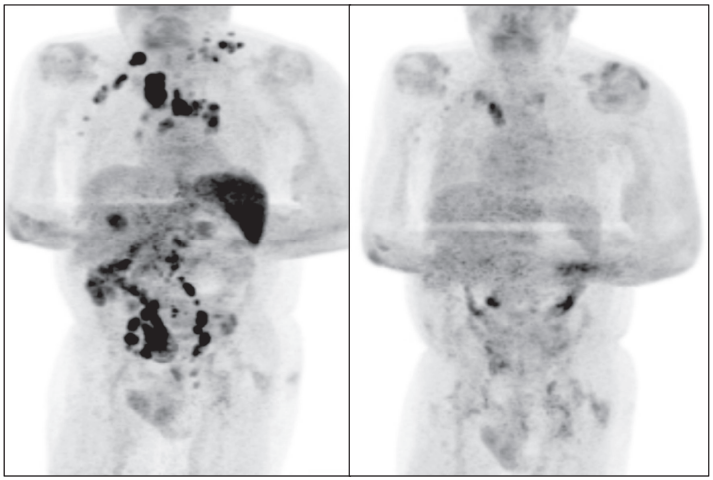

CT检查照片显示:可触及的淋巴结病变减少,淋巴结病变广泛消退,整个区域的代谢摄取减少。

前后对比不要太明显!

左图为最初的PET/CT扫描结果

右图为4个月后的PET/CT扫描结果